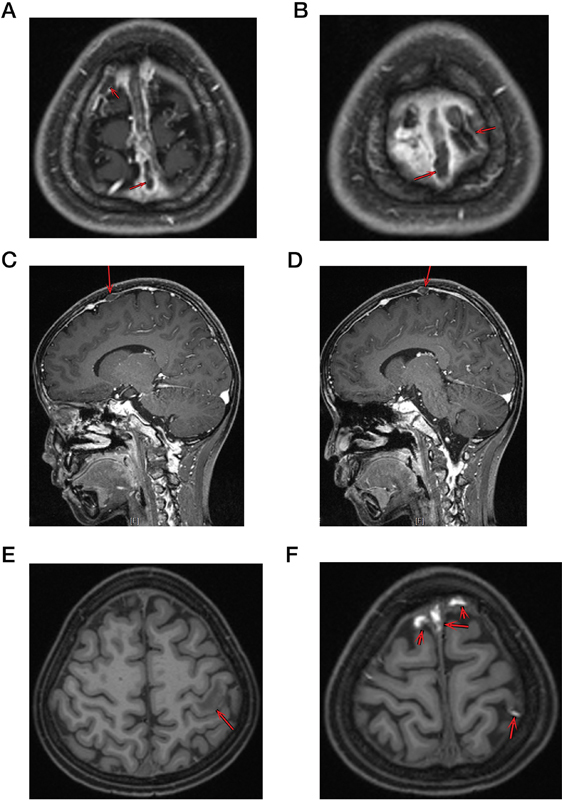

Cerebral venous sinus thrombosis (CVST) and hyperlipidemia are severe complications of L-Asparaginase (L-Asp) during the treatment of B-cell acute lymphoblastic leukemia (B-ALL). Herein, we reported a 9-year-old B-ALL boy who underwent abnormal hypertriglyceridemia and CVST presenting as seizures and disturbance of consciousness twice during the induction therapy. Fortunately, he survived treatment with anticoagulant and lipid-lowering therapy. No thrombophilia-related gene mutation was detected, but a heterozygous mutation in lipoprotein lipase (LPL) gene was identified. His neurological symptoms were managed with short-term anticoagulant therapy and long-term lipid-lowering therapy. This case illustrated the manifestation and potential pathogenesis of CVST and highlighted the essentiality of screening baseline lipid profile and dyslipidemia- and thrombophilia-related gene mutation.